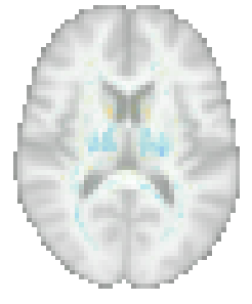

where (cf. A). The predicted value of is therefore given by (6), which again involves taking the inner product of the discriminative weights with . An example of model inversion in case of age prediction is shown in Fig. 2.

Proposed method: We performed all the experiments with the proposed method in Matlab, running on a Linux CPU machine (Intel Xeon E5-2660V3 10 Core CPU 2.60GHz, 128GB RAM). To speed up computations, the number of voxels was reduced by masking out the background (by thresholding the average of all images in each training set), and by downsampling the input data to a 3mm isotropic resolution. This downsampling was found not to affect the prediction performance in pilot experiments. For each training run, performance on the validation set was used to set the number of latent variables , which is the only hyperparameter of the method. An example of a model trained this way is shown in Figs. 3, 4 and 5.